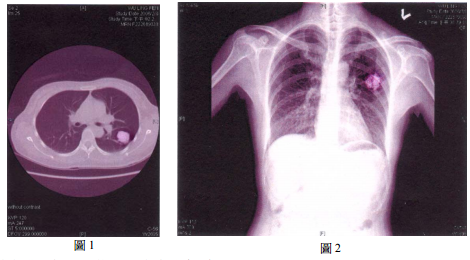

28 一位 38 歲女性,兩年前因為大腸癌做切除術,之後定期在門診追蹤。最近胸部攝影如圖 1、圖 2 所 示,病人原開刀部位無復發現象,除圖示外其它部位無異常。請就最可能的診斷選出最適當的處置: (A) 化學治療 (B)放射治療 (C)開刀切除 (D)光子刀治療

48 (A) 病人需要做化學治療 (B)病情處置以放置氣管內支架為宜 (C)病人手術切除以開胸為宜 (D)腫瘤為良性的機率較大

75 (A) quadrigeminal cistern (B) prepontine cistern (C) suprasellar cistern (D) CP angle cistern 圖1 圖2 圖3